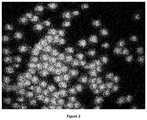

FIG. 1. A micrograph showing a plurality of units according to the disclosure as set forth in Table 2 after admixture with tap water.

A composition according to certain embodiments of the disclosure was mixed with tap water and placed on a Petri dish. The same procedure was performed on a composition with no xanthan gum outer coating (control).FIGS. 1 and 2 show micrographs of the compositions according to certain embodiments of the disclosure as set forth in Tables 2 and 3, respectively, exemplifying the halo formed around each pellet. The halo is indicative of imbibition of water by the outer coating and its swelling.FIGS. 3A-3E show a sequence of micrographs of the composition according to certain embodiments of the disclosure as set forth in Table 7, the micrographs taken at time 0, 100, 200, 300 and 600 seconds after admixture with tap water, respectively. The micrographs exemplify the swelling of the outer coating due to imbibition of water.FIG. 4 shows the absence of halo in a control sample andFIGS. 5A and 5B show the absence of a halo in a control sample at time 0 and 600 seconds after admixture with tap water, respectively.